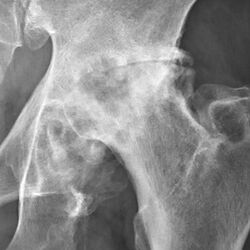

Osteoarthritis of the hip joint may also be graded by Tönnis classification. There is no consensus whether it is more or less reliable than the Kellgren-Lawrence system.[8]

Severe (Tönnis grade 3) osteoarthritis of the hip.

Tönnis classification[9]

| 3 |

Severe:

- large bone cysts

- severe joint space narrowing, or joint space obliteration

- severe deformity of the head

|